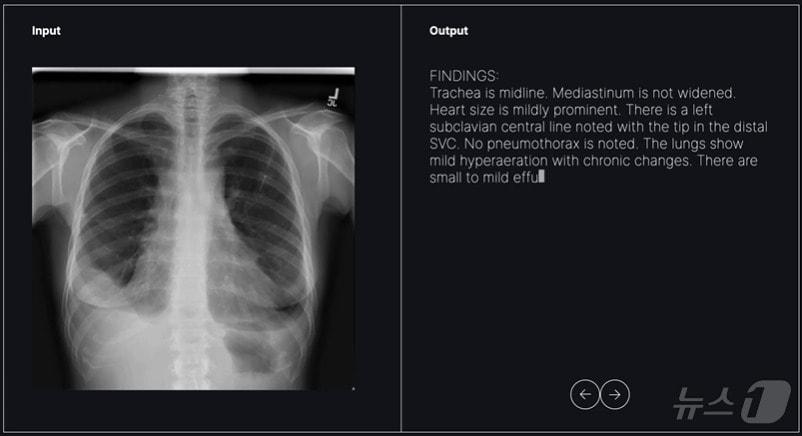

본문 이미지 - 숨빗AI가 개발 중인 영상의학과용 초기 판독문 생성 솔루션 'AI리드-CXR' 활용 모습.(숨빗AI 제공)/뉴스1 ⓒ News1

숨빗AI가 개발 중인 영상의학과용 초기 판독문 생성 솔루션 'AI리드-CXR' 활용 모습.(숨빗AI 제공)/뉴스1 ⓒ News1